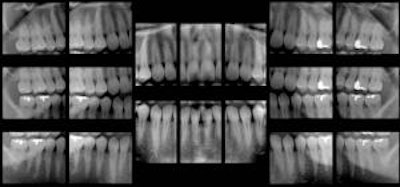

| These panoramic bitewings took 15 to 20 seconds to create, compared with 20 minutes for a full-mouth intraoral survey (Dentomaxillofacial Radiology, January 2010, Vol. 39:1, pp. 47-53). |